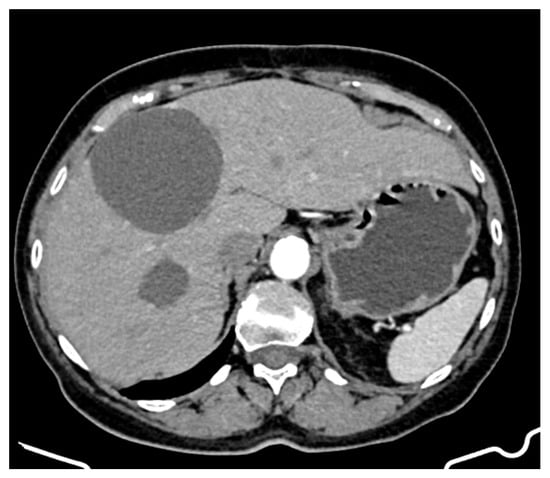

An abdominopelvic CT revealed liver enlargement due to the presence of numerous cystic lesions ranging in size from 1 cm to 18 cm, most of them located in the right hepatic lobe (Figure 1). Two of the largest cystic formations were located at the inferior liver margin, one in segment IVb and the other in segment III of the left hepatic lobe, occupying almost the entire abdominal cavity. The inferior pole of the cystic formation arising from the left hepatic lobe extended into the pelvic cavity (14 × 18 × 18.5 mm AP/Transverse/CC), displacing the transverse colon posteriorly and shifting the jejuno-ileal loops toward the right iliac fossa. The cysts had well-defined contours, but their inner walls varied in thickness and exhibited heterogeneous contrast enhancement. Three hepatic parenchymal calcifications were present in the right hepatic lobe (segments V and VI), with the largest measuring 14 mm and the smallest 2–3 mm; two of them were adjacent to the cystic wall. A thin layer of perihepatic/hepatodiaphragmatic fluid was also noted, with an uneven thickness ranging from 1 to 2.3 cm.

Figure 1.

CT appearance at the time of diagnosis: hepatic tumour formations with a cystic morphology, showing walls of variable thickness and heterogeneous contrast enhancement.